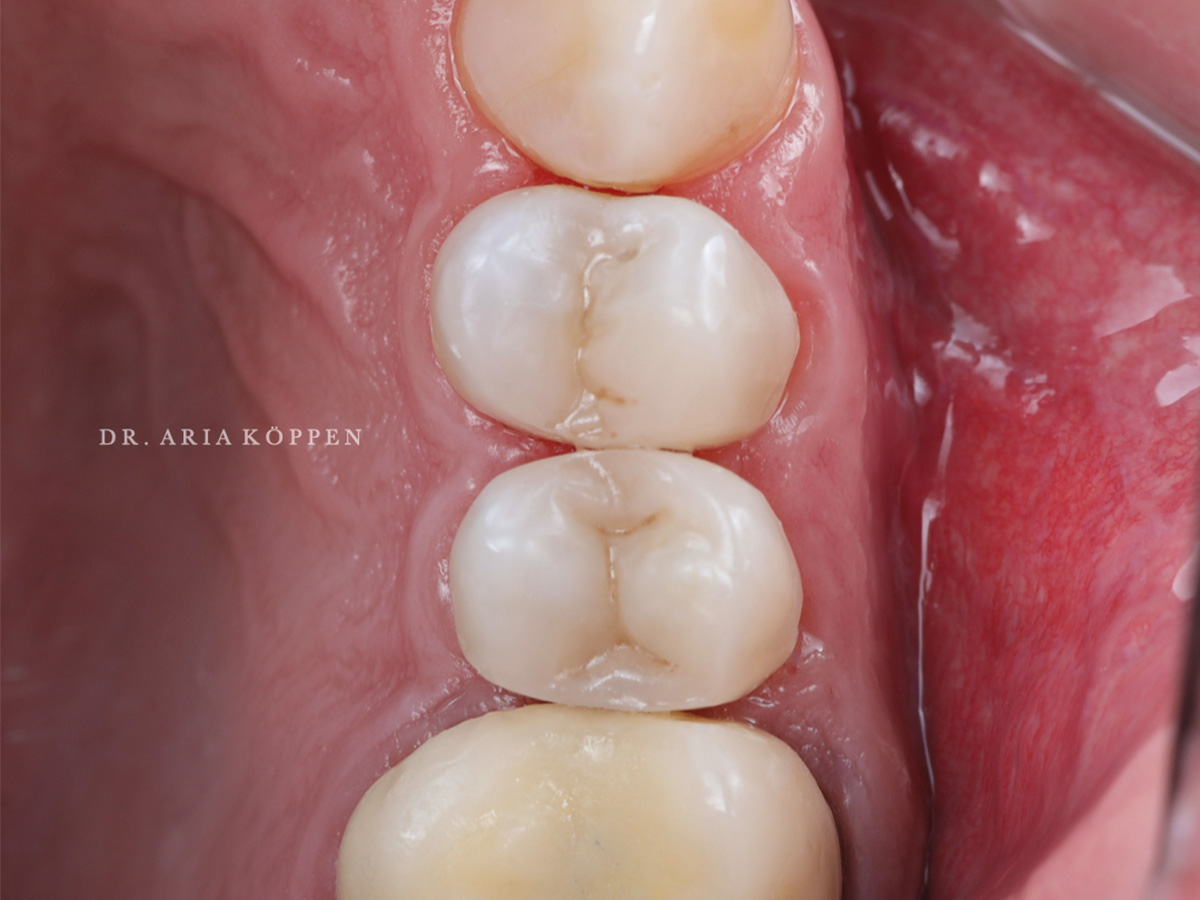

Abbildung 10

Fertigstellung nach Überprüfung der Okklusion.